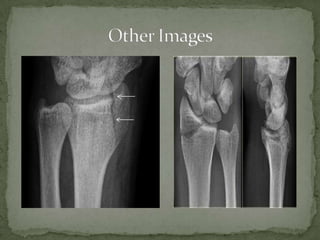

A 45-year-old male presents to the emergency department with right wrist pain after falling on an outstretched hand while working in his yard. On examination, his right wrist is tender over the distal radius with no other deformities or neurological deficits. A chauffeur's fracture is suspected due to the mechanism of injury, which is an avulsion fracture of the radial styloid that often requires surgical fixation. Close orthopedic follow up is needed to properly evaluate and treat the injury.